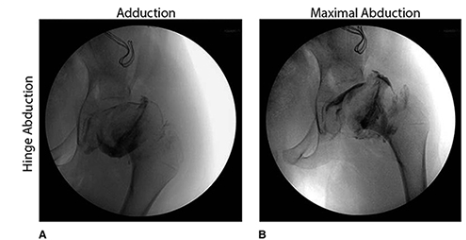

LCPD: what is the significance of hinged abduction and how is it treated?

Hinged abduction, in which lateral extrusion of the femoral head results in it impinging on the edge of the acetabulum with abduction, may be present. Treatment option include the following:

A valgus-flexion proximal femur osteotomy to place the concentric portion in contact with the acetabular roof.

Pelvic osteotomy procedures, such as a Chiari osteotomy, shelf arthroplasty, and shelf acetabuloplasty (labral support procedure), also may be beneficial but have very limited indications